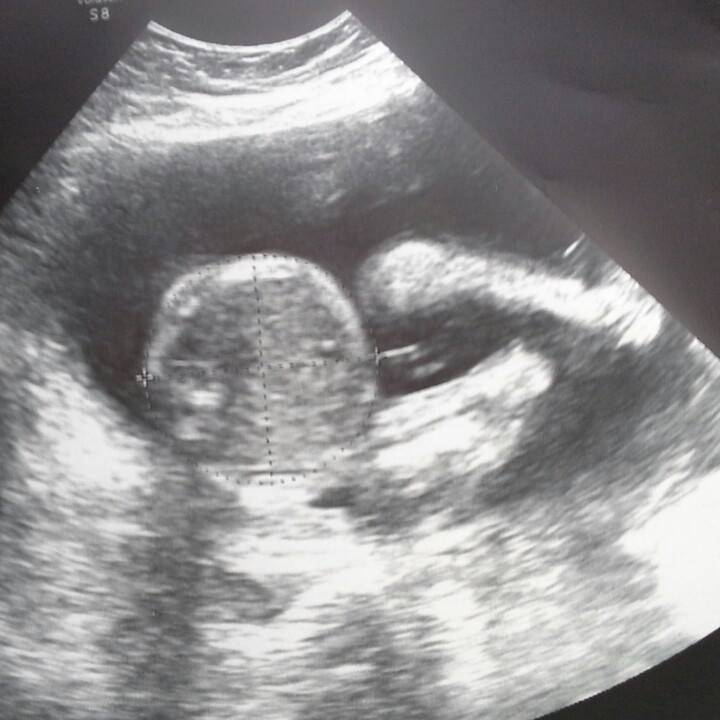

Elisha McGill ha già due bambini, Bobby e Ollie, di 22 e 9 mesi ed è in attesa del terzo figlio. Il bambino o bambina che porta in grembo però è affetto da anencefalia, una malformazione congenita grave, che si può riscontrare già durante il primo mese di gravidanza, e dove il nascituro appare privo totalmente o parzialmente della volta cranica e dell’encefalo. La gravidanza è alla sua 18esima settimana, ma il feto non ha alcuna speranza di vivere a lungo, spesso i neonati muoiono durante il parto in pochi riescono a vivere solo alcuni minuti, ed in casi rarissimi sopravvivono alcuni mesi.

Ma i genitori McGill non hanno mai nutrito alcun dubbio. Elisha sarebbe arrivata fino alla 36esima settimana, quando il piccolo McGill potrebbe venire alla luce, in modo che i suoi organi possano essere espiantati. Proprio Elisha ha dichiarato queste parole al Belfast Telegraph:

“Non importa quanto tempo il piccolo vivrà, noi gli daremo tutto il nostro amore di genitori. Noi speriamo di far arrivare il nostro piccolo alle 36 settimane e poi coccolarlo per i pochi minuti che ci saranno concessi, infine ci auguriamo che parte di lui possa continuare a vivere in altri bambini”.

“Siamo a metà percorso, 18 settimane su 36, il piccolo ha cominciato a tirare i primi calci è emozionante sentire come lotta per la vita, sua e di altri bambini come lui. Non vedo l’ora di poter dire a tutti il suo nome e poi poterlo cullare tra le mie braccia. Per giorni, ore, o anche solo qualche secondo”.